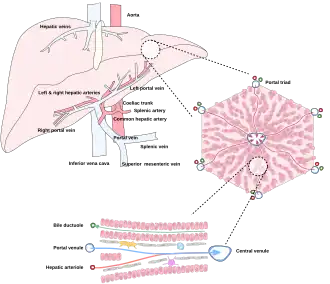

Microscopic anatomy

Microscopically, each liver lobe is seen to be made up of hepatic lobules. The lobules are roughly hexagonal, and consist of plates of hepatocytes, and sinusoids radiating from a central vein towards an imaginary perimeter of interlobular portal triads.[24] The central vein joins to the hepatic vein to carry blood out from the liver. A distinctive component of a lobule is the portal triad, which can be found running along each of the lobule's corners. The portal triad consists of the hepatic artery, the portal vein, and the common bile duct.[25] The triad may be seen on a liver ultrasound, as a Mickey Mouse sign with the portal vein as the head, and the hepatic artery, and the common bile duct as the ears.[26]

Histology, the study of microscopic anatomy, shows two major types of liver cell: parenchymal cells and nonparenchymal cells. About 70–85% of the liver volume is occupied by parenchymal hepatocytes. Nonparenchymal cells constitute 40% of the total number of liver cells but only 6.5% of its volume.[27] The liver sinusoids are lined with two types of cell, sinusoidal endothelial cells, and phagocytic Kupffer cells.[28] Hepatic stellate cells are nonparenchymal cells found in the perisinusoidal space, between a sinusoid and a hepatocyte.[27] Additionally, intrahepatic lymphocytes are often present in the sinusoidal lumen.[27]

Blood supply

The liver gets its blood supply from the hepatic portal vein and hepatic arteries. The hepatic portal vein delivers around 75% of the liver's blood supply and carries venous blood drained from the spleen, gastrointestinal tract, and its associated organs. The hepatic arteries supply arterial blood to the liver, accounting for the remaining quarter of its blood flow. Oxygen is provided from both sources; about half of the liver's oxygen demand is met by the hepatic portal vein, and half is met by the hepatic arteries.[46] The hepatic artery also has both alpha- and beta-adrenergic receptors; therefore, flow through the artery is controlled, in part, by the splanchnic nerves of the autonomic nervous system.

Blood flows through the liver sinusoids and empties into the central vein of each lobule. The central veins coalesce into hepatic veins, which leave the liver and drain into the inferior vena cava.[47]

The liver and its veins -

Diagram of liver, lobule, and portal tract and their inter-relations